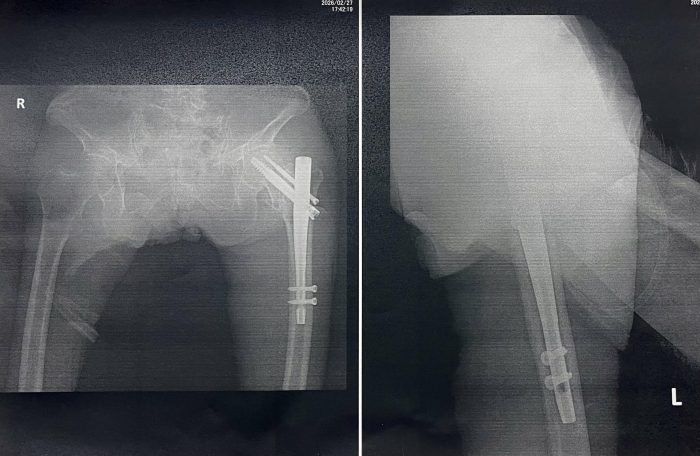

手術後に見せてもらったレントゲン写真には、太ももの骨の中心に金属の棒が通り、上下をスクリューで固定した姿が写っていました。これは 髄内釘(インターロッキング・ネイル) と呼ばれ、折れた骨を内側から支えるための“芯”のような存在です。